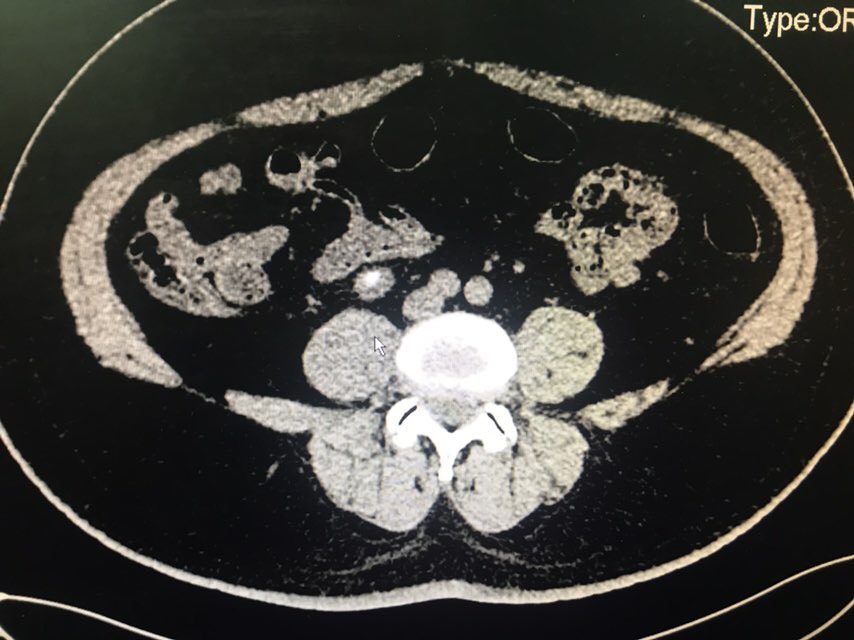

查体:无特殊。辅助检查:全腹CT(我院2018-8-6):右肾盂、肾盏及右输尿管上段明显扩张、积水;右侧输尿管置管。左肾盏区点状结石;双肾囊肿可能。膀胱充盈,壁稍增厚、毛糙,合并炎症可能,胆囊结石。脂肪肝;肝右叶小钙化灶。

从患者CT片子上看,患者右侧输尿管下段狭窄,输尿管支架管返折,因膀胱镜下未能成功取出,故行右侧输尿管探查术。手术顺利,术后给予曲克芦丁脑蛋白水解物注射液5ml治疗,患者术后恢复良好。